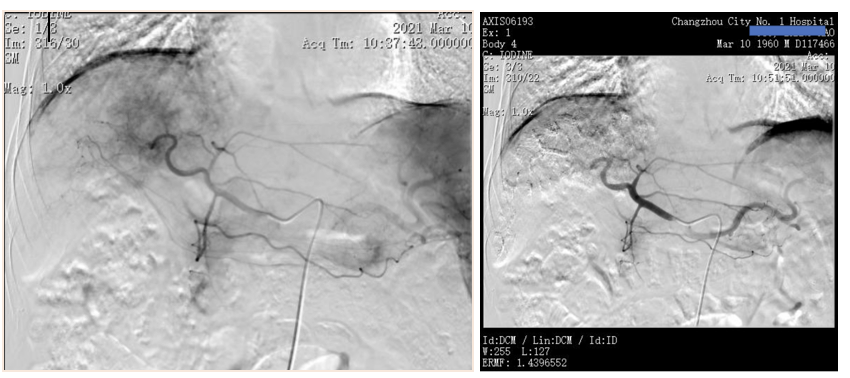

2021年10月18日AFP为443.9ng/ml。2021年10月20日复查CT示,肾上腺病灶较前明显增大,髂骨病灶缩小(图8)。

图8.2021年10月20日复查CT

2021年12月20日复查CT示,右侧肾上腺病灶明显缩小,髂骨病灶也进一步缩小(图9)。

图9.2021年12月20日复查CT

2022年1月18日复查MR提示,肝左叶基本看不到明显的活性病灶,较2020年11月MR明显好转(图10)。

图10.2022年1月18日复查MR

2022年2月8日复查CT提示,肺部病灶基本消失(图11),肾上腺病灶明显缩小,髂骨病灶进一步退缩(图12)。2022年2月9日AFP为411ng/ml。

图11.2022年2月8日复查胸部CT

图12.2022年2月8日复查CT